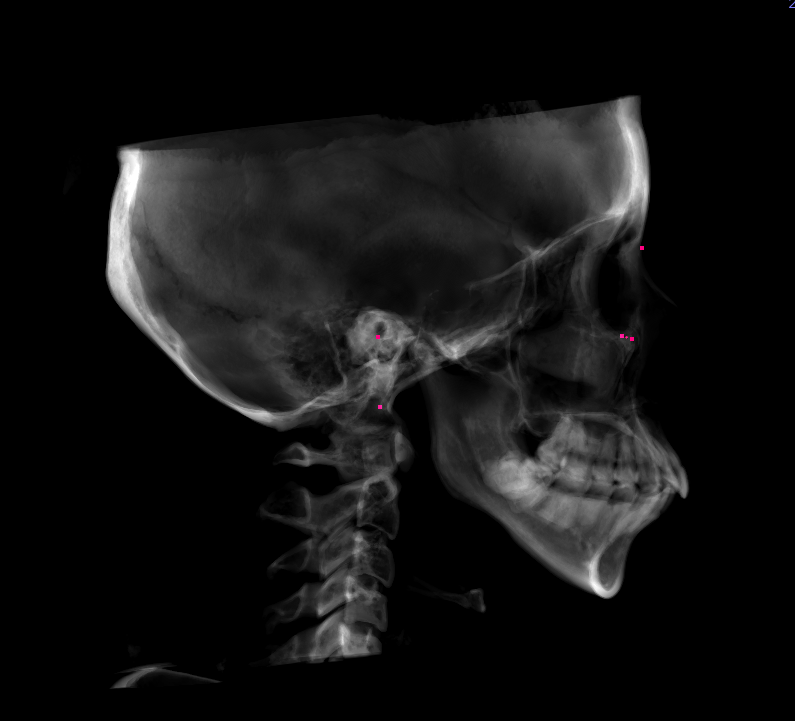

初診時の画像

結論から述べると、部分矯正だけで前歯のガタガタと出っ歯を両方とも治療するのはかなり困難です。前歯のガタガタの原因は歯の大きさと顎の大きさのバランスが悪いために前歯が綺麗に並ばないのです。顎を満員電車に例えると満員電車にさらに人が入ろうとしてぎゅうぎゅうになってしまっているのです。このような場合には①抜歯を行う、②歯を削って小さくする+歯並びを少し拡大するといった治療を行うことでガタガタを解消します。しかし、今回のように出っ歯もガタガタも気になる場合には、基本的には抜歯を行わなければ、歯を内に入れてガタガタを解消することができないのです。抜歯を行う場合は基本的には部分矯正では治療を行えませんので、今回K.Kさんの場合は全体の矯正治療が必要になります。

今回の症例では、前歯部の叢生および上顎前突を主訴に来院された患者様のご相談内容でした。